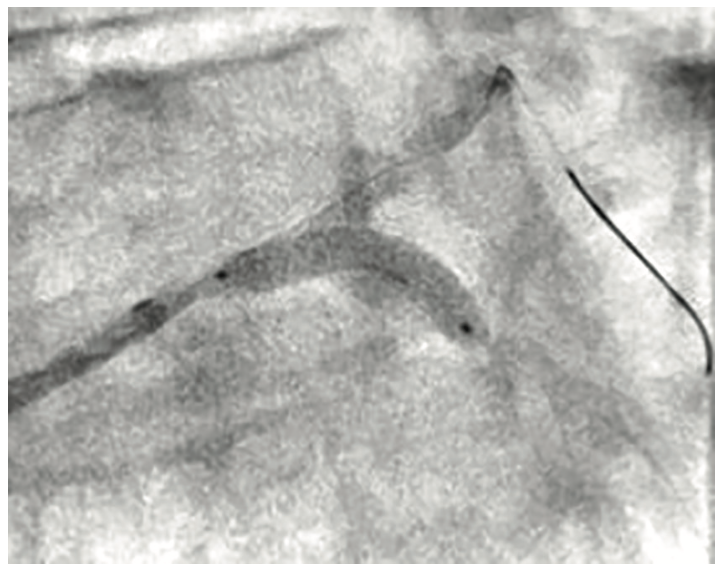

Right radial access was obtained with a radial 7 French (Fr), 10 cm length GLIDESHEATH SLENDER® Introducer Sheath (Terumo Interventional Systems) and the ostium of the LMCA was engaged with a 7 Fr Extra Backup (EBU) 3.5 guide catheter (Medtronic) to facilitate bifurcation stenting. The initial angiogram images revealed a worsening of the distal LMCA stenosis, now at 80% and extending into the ostial LAD (Figure 1). A Runthrough NS Izanai White guidewire was advanced across the lesion into the distal LAD and a Runthrough NS Izanai Blue was advanced across the lesion into the distal LCx with minimal difficulty. To facilitate intravascular ultrasound catheter delivery, the distal LMCA/ostial LCx was predilated with a semicompliant 2.0 mm x 15 mm Takeru PTCA Balloon Dilatation Catheter at nominal pressure (8 atmospheres). IVUS of the LCx was performed first, followed by IVUS of the LAD, and showed severe, concentric calcification of the distal LMCA and ostial LAD/LCx (Figure 2). For plaque modification and lesion optimization prior to stent deployment, a 3.5 mm x 12 mm C2+ intravascular lithotripsy balloon (IVL, Shockwave Medical) was advanced first into the LCx and subsequently into the LAD. The LMCA to proximal LCx and the ostial LAD were treated with 120 pulses with 12 inflations of the IVL balloon. Angiography revealed no evidence of dissection following IVL; however, there was some recoil in the ostial LCx, for which cutting balloon angioplasty was performed with a 3.5 mm x 15 mm Wolverine balloon (Boston Scientific) in the ostial LCx and extending back into the distal left main. Next, the decision was made to proceed with bifurcation stenting using a culotte strategy. A 3.5 mm x 20 mm Synergy Megatron drug-eluting stent (DES, Boston Scientific) was placed from the distal LMCA into the proximal LCx (Figure 3). Following post dilation of the DES with a 3.5 mm x 15 mm noncompliant balloon, a new Runthrough NS Izanai White was used to re-wire the LAD through a side strut of the LMCA-LCx DES. A semicompliant 3.0 mm x 12 mm Takeru PTCA Balloon Dilatation Catheter crossed into the LAD with minimal difficulty and was used to dilate the stent struts to facilitate delivery of the LMCA-LAD DES. A noncompliant 3.0 mm x 15 mm balloon inflation was performed to optimize the LAD lesion further. A 3.5 mm x 16 mm Synergy Megatron DES was then placed in the proximal LAD, overlapping with the prior stent in the LMCA (Figure 4). Following post dilation of the LMCA-LAD DES with a 3.5 mm x 15 mm noncompliant balloon, the proximal portion was optimized (proximal optimization technique [POT]) with a 4.0 mm x 8 mm noncompliant balloon. The LCx was then rewired with the Runthrough NS Izanai White through a side strut of the LMCA-LAD stent and the Runthrough NS Izanai Blue was placed in the LAD. Following serial dilations of the LMCA-LAD stent struts with Takeru PTCA Balloon Dilatation Catheters, kissing balloon inflation of both the LAD and LCx extending back into the LMCA was performed with a 3.5 mm x 15 mm noncompliant balloon in the LCx and a 3.0 mm x 15 mm noncompliant balloon in the LAD (Figure 5). Repeat IVUS of both stents back into the LMCA was performed, demonstrating adequately expanded and apposed stents with no evidence of edge dissection. Final POT was performed in the LMCA with a 4.5 mm x 8 mm noncompliant balloon. Final angiography revealed TIMI-III flow, no evidence of proximal or distal edge dissections, no perforation, and <5% residual stenosis (Figure 6). The total contrast volume was 55 mL with a case length of 1.5 hours. The patient was discharged three days later without complication.